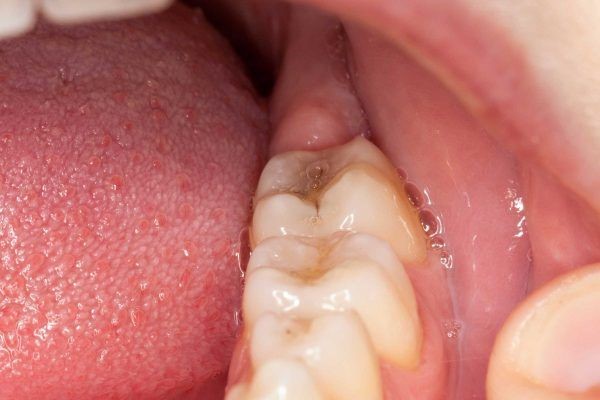

Răng khôn là răng mọc muộn và nằm sâu trong cung hàm. Do mọc trễ và thiếu chỗ trống nên chúng thường có xu hướng mọc ngầm, mọc nghiêng, mọc lệch sang răng số 7 dẫn đến tình trạng lợi trùm, sâu răng, viêm tủy hoặc làm mất răng số 7.

(Bị lợi trùm do mọc răng khôn là tình trạng thường gặp)(**)